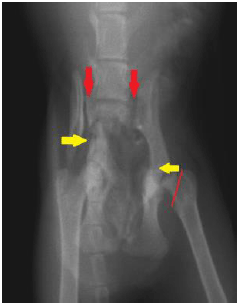

![]() |

交通事故後のレントゲン写真で、子猫の骨盤が正面から映っています。 本来くっついているはずの骨盤と腰骨がずれて脱臼しています。(赤矢印) 骨盤そのものも折れています。(黄矢印) |

手術後のレントゲン写真です。 骨盤と腰骨の脱臼を直し、骨盤の骨折も元に戻して固定しました。 太ももの骨の付け根は、一つ前の写真の赤線のラインで切り落としてあります。 「骨を切り落とす」というと痛くて残酷そうにも思えますが、実際にはこの逆で、この処置を行わないと痛みが取れず、子猫が辛い思いをすることになります。 この子は無事に成長し、現在は元気に走り回っています! |